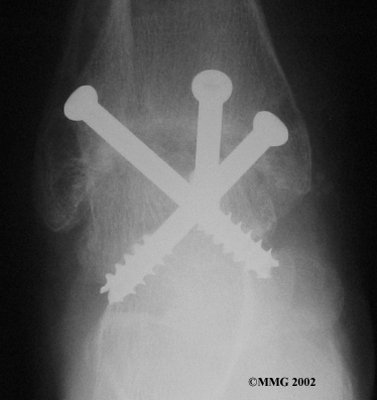

It is important when the surfaces are removed that the angles of the cut surfaces are correct. When the tibia is brought against the talus, the foot should be at a right angle to the lower leg. Once the cuts are made the bones must be held in place while they fuse. This can be done using large metal screws and metal plates if necessary. The screws are usually under the skin and are not removed unless they begin to rub and cause pain.

Inserting the screws

After ankle fusion, the physical therapists at FYZICAL Travelers Rest can help you learn to walk smoothly and without a limp. Although time needed for recovery varies among patients, an ankle brace will typically replace your cast after eight to 12 weeks. Your surgeon will take X-rays frequently to see if the bones are fusing together. You will probably need to use crutches during the time you wear the cast. As the fusion grows stronger, you will begin to put more weight on your foot when walking.